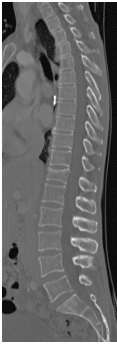

48 yo Female had a sledding injury when she landed on her buttocks following a fall. She felt a “pop” and immediate back pain. She was able to walk briefly, but quickly incapacitated by pain. Her examination suggested an injury to the lower thoracic spine. She was neurologically intact. She had uncontrolled pain. X Rays and CT scan of the patient showed fracture of T12 vertebral body.

The fracture was stabilized by Minimal Invasive spine surgery with percutaneous pedicle screws in T11, 12 and L1 and rod fixation.